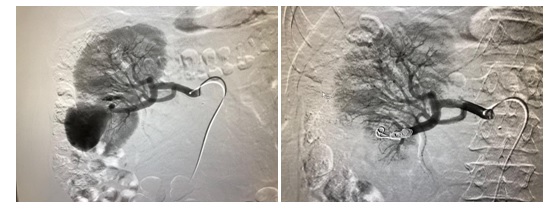

Wskaż fałszywe stwierdzenie dotyczące powikłania po przeszczepieniu nerki widocznego na zdjęciu: